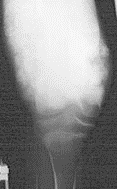

Giant cell tumor relatively uncommon, locally aggressive neoplasm that may produce bone destruction and soft tissue destruction 20-50 years 65% in distal femur, proximal tibia, and distal radius well-defined, lytic lesion eccentrically located in epiphysis with subchondral and metaphyseal extension